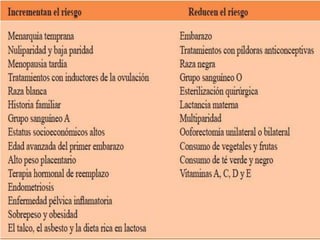

Pase para saber Psicológico pueblo Marcadores tumorales en el diagnóstico de cáncer epitelial de ovario: caso de estudio Tumor markers in the diagnosis of epit